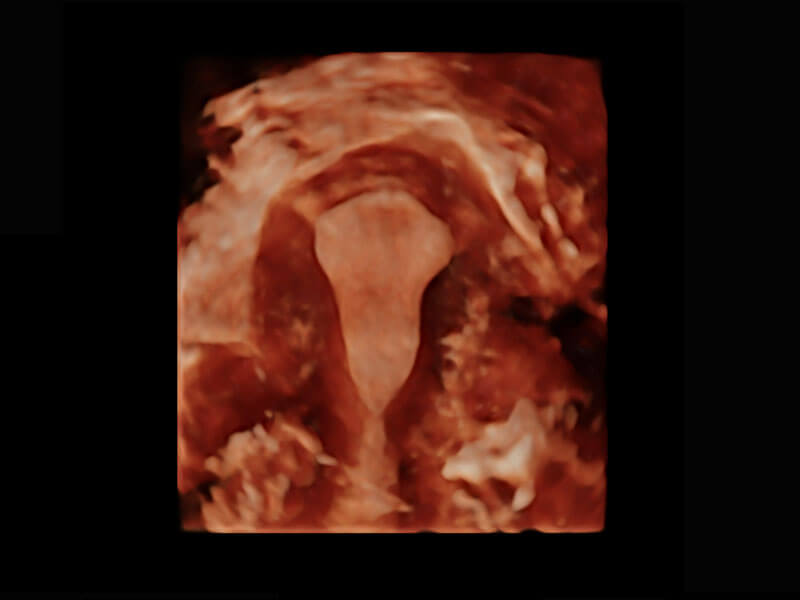

P60優(yōu)異的圖像質(zhì)量搭載專科探頭,在婦科基礎(chǔ)疾病的診斷、卵泡生長(zhǎng)的監(jiān)測(cè)、輸卵管通暢情況的判別等方面為您提供生殖應(yīng)用方案。

腔內(nèi)三維-宮內(nèi)節(jié)育器